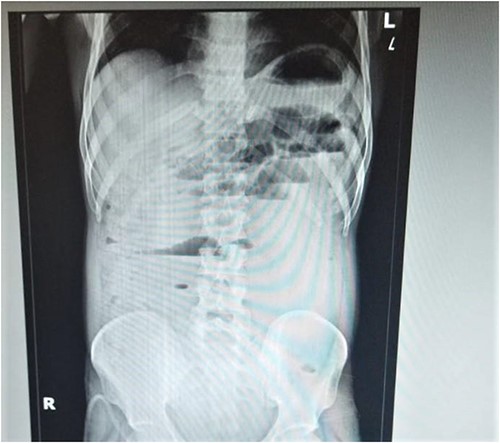

A computed tomography (CT) scan of the abdomen revealed moderate dilation of the proximal and mid- to small bowel loops, with a transition point in the pelvic ileal loop, indicating small bowel obstruction and gall bladder distension. Immediately Elective Sigmoidectomy was performed, and the patient had an uncomplicated postoperative recovery lasting for 25 days. However, the patient subsequently presented to the emergency department with symptoms of acute obstruction. The erect abdominal X-ray reveals air-fluid levels, indicating the presence of fluid and air accumulation in the proximal large bowel and terminal ileum (Fig. 1). Following a thorough evaluation, the patient underwent an exploratory laparotomy. Intraoperatively, multiple adhesions between the loops of the bowel and identified a thick band at the terminal ileum (Fig. 2). Adhesiolysis (surgical removal of adhesions) was performed, and the patient experienced a smooth recovery without any complications till date. The patient’s prior surgical history of sigmoidopexy and sigmoidectomy is relevant to understanding multiple adhesions and subsequent occurrences of sigmoid volvulus.

The erect abdominal X-ray reveals air-fluid levels, indicating the presence of fluid and air accumulation in the proximal large bowel and terminal ileum.